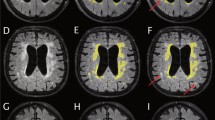

TBSS analyses

The comparison between FA maps for the SR group at baseline and the HC group and the regional peaks for significant clusters (t value >2.0) are demonstrated in Fig. 3 and Table 3A. The FA values of the SR group were significantly lower in the middle and posterior parts of the cingulum, genu, body, and splenium of the corpus callosum, the crus of the right fornix, and the subcortical white matter (SWM) of the right frontal operculum, right precuneus, bilateral superior parietal lobules, right occipital cortex, right primary motor cortex, and left primary motor cortex. However, as the result of the back-projection, the back-projected voxels in a peri-Sylvian portion of the SWM of the right frontal operculum were positioned on the right Sylvian fissure (incidence: HC 4/10; SR 19/20; SNR 4/10), and those in the crus of the right fornix were on the right lateral ventricle or right thalamus (incidence: HC 9/10; SR 20/20; SNR 8/8). Therefore, these regions were excluded from the FA data set. There were no regions in which the SR group presents significantly higher FA values than the HC group. In addition, there were no regions in which the FA values were significantly different between the SNR group and the HC group and between the SR group and SNR group (data not shown).

White matter regions in which FA values were significantly lower in shunt-responsive INPH. The areas with significantly lower FA values are demonstrated by colours ranging from blue to light-blue in the shunt-responsive INPH patients compared to control subjects (p < 0.05, corrected for multiple comparisons by using TFCE). The mis-registered regions are shown in white. A anterior, L left, P posterior

Figure 4 and Table 3B show the results of the group comparison for MD between the baseline SR and HC groups and the regional peaks for significant clusters (t value >2.0). The MD values of the SR group were significantly higher in the columns, bodies, and crura of the bilateral fornixes, the hippocampal part of the right cingulum, the genu, body, and splenium of the corpus callosum, and the subcortical white matter (SWM) of the bilateral frontal operculum, bilateral orbitofrontal cortex, bilateral primary motor and sensory cortex, posterior part of temporal cortex, bilateral superior and inferior parietal lobules, right precuneus, and right occipital cortex, as well as the right external capsule, the bilateral cerebral peduncles, and the bilateral internal capsules. However, as a result of the back-projection, the back-projected voxels in the columns, bodies, and crura of the bilateral fornixes were positioned on each side of the lateral ventricle (incidence: HC 10/10; SR 20/20; SNR 8/8), those in a peri-Sylvian portion of the SWM of bilateral frontal operculums were on each side of the Sylvian fissure [incidence (right): HC 5/10; SR 20/20; SNR 8/8, incidence (left): HC 0/10; SR 20/20; SNR 8/8], and those in the SWM of posterior part of the right temporal cortex were on the right Sylvian fissure (incidence: HC 0/10; SR 20/20; SNR 8/8). Therefore, these regions were excluded from the MD data set (Fig. 1b). There were no regions in which the SR group presented a significantly lower MD than the HC group. Furthermore, there were no regions in which the MD values were significantly different between the SNR group and the HC group and between the SR group and SNR group (data not shown).

White matter regions in which MD values were significantly higher in shunt-responsive INPH. The areas with significantly higher MD values are demonstrated by colours ranging from red to yellow in the shunt-responsive INPH patients compared to control subjects (p < 0.05, corrected for multiple comparisons by using TFCE). The mis-registered regions are shown in white. A anterior, L left, P posterior

On the other hand, the results of back-projection revealed the precise registration of the corpus callosum, the cerebral peduncles, the internal capsule, the corona radiata, and the SWM except for the frontal and temporal operculum. The DTI measures of the corpus callosum and the CST using the TBSS were validated by anatomical ROI analysis in several previous studies [10, 15]. The results of the current study suggested that the TBSS is a useful tool for detecting white matter abnormalities in these regions.

FA values in the corpus callosum and in the SWM of the convexity and occipital cortex were significantly lower in SR than in HC, whereas MD values in the periventricular and peri-Sylvian white matter were significantly higher. These findings were frequently reported in the previous DTI studies [10, 15]. The white matter regions in which FA values were decreased after shunt placement were distributed in the left corona radiata. These regions were located between the lateral ventricle and the Sylvian fissure, and therefore may have been severely compressed. Recent studies reported that the FA values of the CST near the lateral ventricles in INPH were higher compared with those in healthy controls, although this result was not confirmed in the present study [10, 11]. Hattori et al. detected the increase of axial eigenvalues and unaltered radial eigenvalues in the CST and suggested that mechanical pressure from ventricular dilatation could enhance directional water diffusivity parallel to the axon in the CST in INPH [11]. In addition, we speculated that dilatation of the Sylvian fissures could play a role of counterfort against mechanical pressure from the ventricular dilatation in INPH. It is considered that the release of compression to the corona radiata including the CST and projection fibre to the medial frontal cortex, which is thought to play a role in planning or programming voluntary movements including gait, is associated with clinical improvement after shunt placement [9, 33, 34].